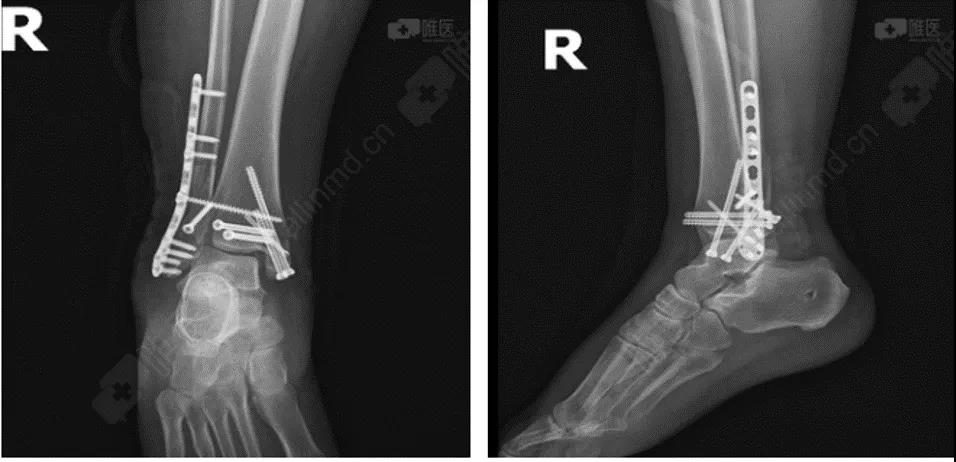

术后DR

复位固定顺序